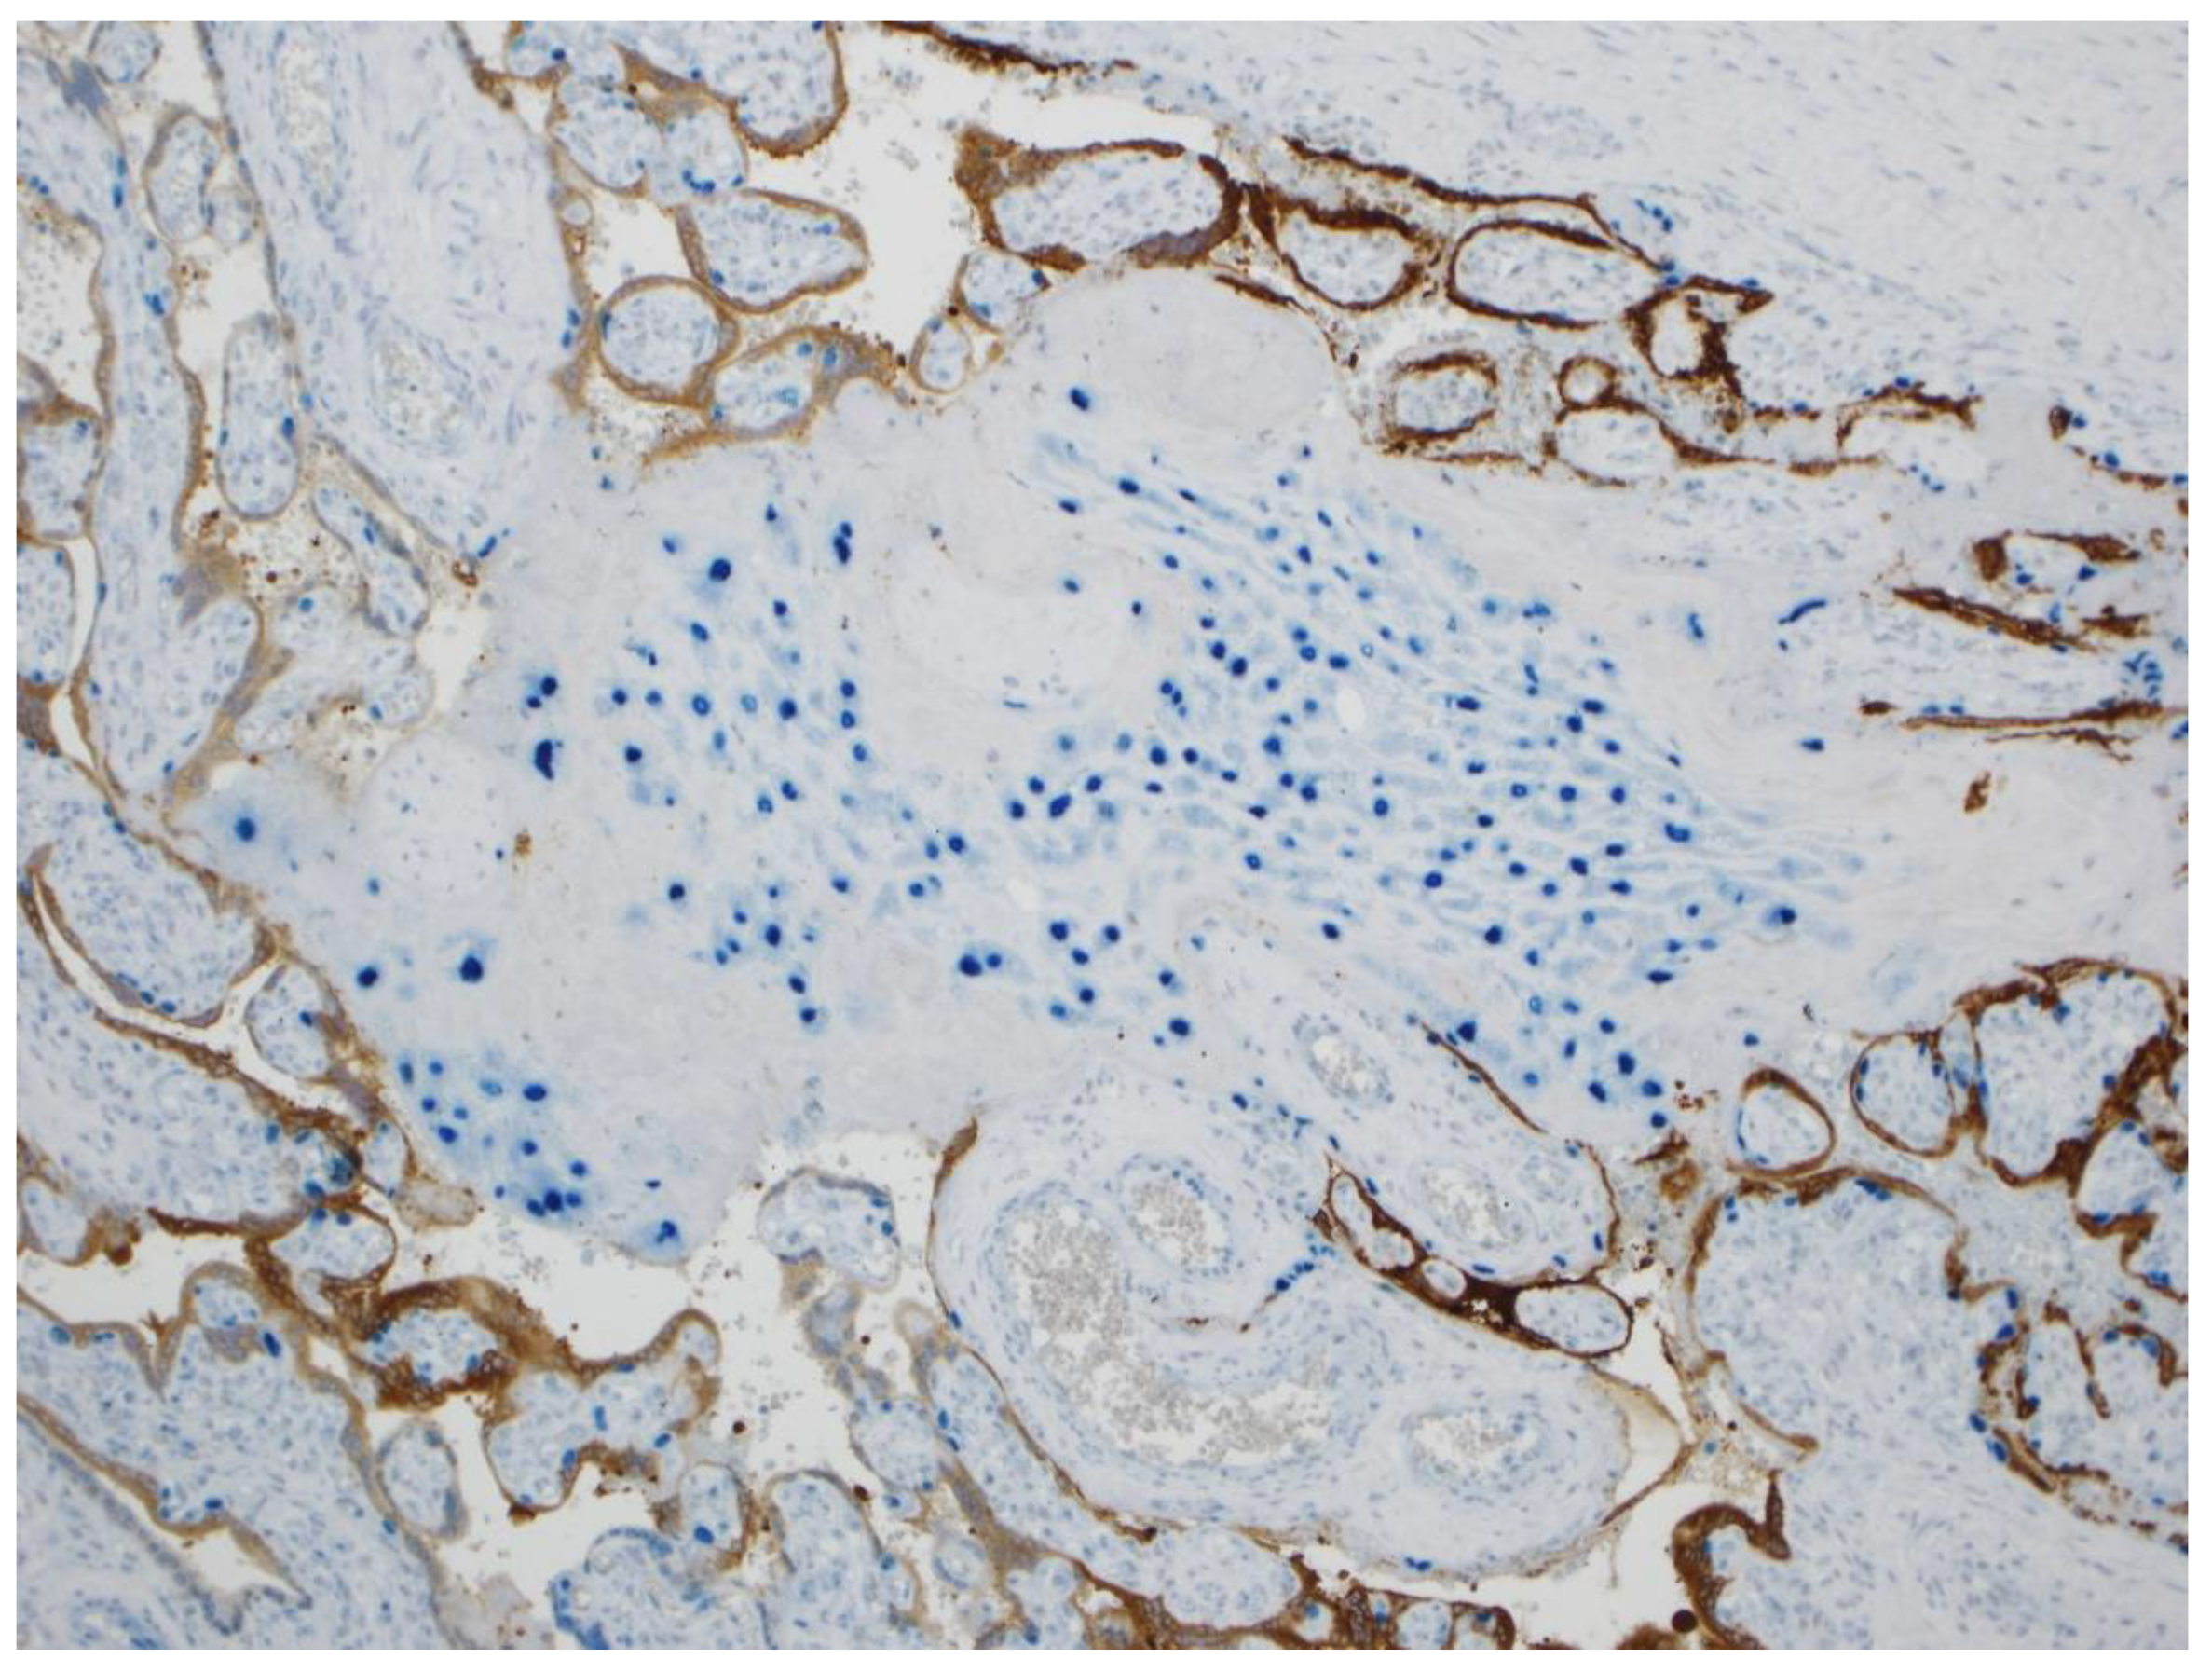

Molecular Pathology Demonstration of SARS-CoV-2 in Cytotrophoblast from Placental Tissue with Chronic Histiocytic Intervillositis, Trophoblast Necrosis and COVID-19

- Schwartz, D.A.; Thomas, K.M. Characterizing COVID-19 maternal-fetal transmission and placental infection using comprehensive molecular pathology. EBioMedicine 2020, 60, 102983. [Google Scholar] [CrossRef]

- Schwartz, D.A.; Morotti, D. Placental pathology of COVID-19 with and without fetal and neonatal infection: Trophoblast necrosis and chronic histiocytic intervillositis as risk factors for transplacental transmission of SARS-CoV-2. Viruses 2020, 12, 1308. [Google Scholar] [CrossRef]

- Schwartz, D.A.; Baldewijns, M.; Benachi, A.; Bugatti, M.; Collins, R.R.J.; De Luca, D.; Facchetti, F.; Linn, R.L.; Marcelis, L.; Morotti, D.; et al. Chronic histiocytic intervillositis with trophoblast necrosis are risk factors associated with placental infection from coronavirus disease 2019 (COVID-19) and intrauterine maternal-fetal severe acute respiratory syndrome coronavirus 2 (SARS-CoV-2) Transmission in liveborn and stillborn infants. Arch. Pathol. Lab. Med. 2021, 145, 517–528. [Google Scholar] [CrossRef]

- Schwartz, D.A.; Baldewijns, M.; Benachi, A.; Bugatti, M.; Bulfamante, G.; Cheng, K.; Collins, R.R.J.; Debelenko, L.; De Luca, D.; Facchetti, F.; et al. Hofbauer cells and coronavirus disease 2019 (COVID-19) in pregnancy: Molecular pathology analysis of villous macrophages, endothelial cells, and placental findings from 22 placentas infected by severe acute respiratory syndrome coronavirus-2 (SARS-CoV-2) with and without fetal transmission. Arch. Pathol. Lab. Med. 2021. [Google Scholar] [CrossRef]